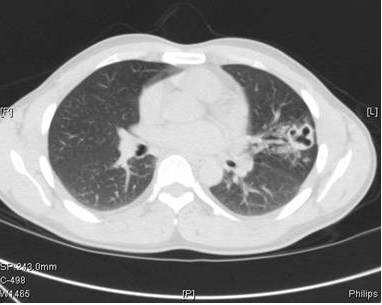

图2: 出现症状是的胸部CT(进行4个月的抗结核治疗)

肺吸虫囊肿通过BAL和支气管镜活检证实。

肺结核是不可能有几次AFB 培养转阴。经纤维支气管镜肺泡灌洗也有几次阴性的AFB染色和培养。此外,虽然进行多种抗结核药物治疗,但空洞恶化。急性支气管炎不是肺空洞的常见原因。

与肺结核相反,肺吸虫病很少伴有啰音或偶发呼吸音。急性期(侵袭和转移)可表现为腹泻、腹痛、发热、咳嗽、荨麻疹、肝脾肿大、肺部异常,外周和BAL样本中嗜酸性粒细胞增多。肺吸虫侵袭和迁移的时期的急性期包括腹痛、腹泻和荨麻疹,随后大约1到2周后出现发热、胸膜炎性胸痛、咳嗽和/或呼吸困难。在慢性期,肺部症状较轻,并有咳嗽、咯血痰,痰液变色,和胸片异常。影像学异常包括胸腔积液、局灶性纤维化胸膜增厚、胸膜下结节,实质性团块,迁移性浸润、空洞性病变、印戒征,少见气液平。最常见的有症状的肺外部位是中枢神经系统。大脑中的吸虫可导致剧烈头痛、头晕、视力障碍。慢性感染可表现为癫痫发作、瘫痪或精神发育迟滞。